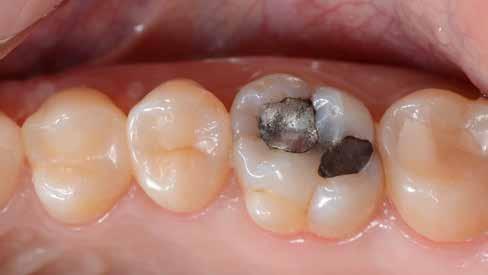

10. ábra: Felső első moláris elégtelen amalgámrestaurációval és II. osztályú carieses lézióval. – 11. ábra: Az érintett kvadráns izolálása kofferdámmal.

Egy 31 éves férfi páciens jelentkezett a jobb felső első molárisából kiinduló, reverzíbilis pulpitisre utaló tünetekkel. A klinikai vizsgálat során meglévő okkluzo-palatinális ezüsta-

malgám restauráció volt észlelhető, valamint szekunder caries mesiálian, a marginális gerinc kavitációjával együtt (10. ábra). A mesio-bukkális csücsök csúcsán kopási fazetta volt látható; a fog egyébként klinikailag és radiológiailag épnek bizonyult. A tájékoztatáson alapuló beleegyezést követően a kezelési terv II. osztályú, háromfelszínű direkt kompozit restauráció volt.

2. ábra: A páciens egy nem megfelelő I. osztályú ezüstamalgám töméssel és II. osztályú szuvasodással jelentkezett. A fog izolálása kofferdám alkalmazásával történt.

3. ábra: A preparálás, a bondozás és a kompozit felvitele után. (Megjegyzés: némi kompozit túlfolyás látható a mesiális doboz axiális falain).